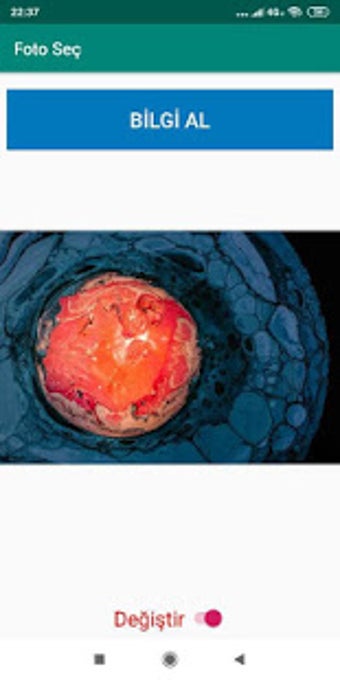

SERSER tarafından Android için ücretsiz bir uygulama.

Foto Seç, 'Yardımcı Programlar ve Araçlar' kategorisinin bir parçası olan Android için ücretsiz bir uygulamadır.

Android için Foto Seç Hakkında

Bu yazılım 18 Haziran 2019'da Softonic'te yayınlandı ve henüz test edemedik.

Denemenizi ve bize bir yorum bırakmanızı veya web sitemizde buna değer vermenizi öneririz. Bu, diğer kullanıcılarımıza çok yardımcı olacaktır!

Foto Seç, Android 9.0 veya üzeri sürümlerde çalışır. Programın güncel sürümü 1.0 olup, sadece Türkçe olarak edinebilirsiniz.